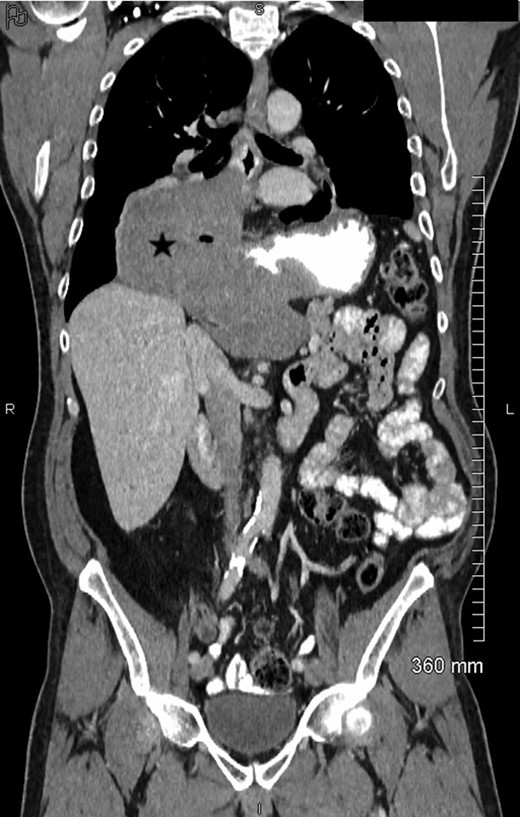

Blood test revealed elevated inflammatory markers (white cell count 21.49 g/L, C reactive protein 359 mg/L, Fibrinogen 7.4 g/L). An abdominal CT-scan showed a recurrence of digestive tumor in pelvis with a digestive presacral fistulization without circumscribed fluid collection. A sagittal section abdominal CT and magnetic resonance imaging (MRI) (Figs. 1–2) showed colic fistula to the presacral collection measured to 38.8 × 9.54 mm with infiltration of adjacent soft tissue and which continues to the spinal canal through the sacral S1 left hole with multiple epidural abscess from L4 to S4. There was osteitis of the sacrum and arachnoiditis.

Axial view contrast-enhanced MDCT (portal phase) with oral opacification, in a x year-old men with a large esophageal GIST, showing a lesion (★), well-circumscribed, with small calcifications (è) (rare). The lesion is homogeneous (no kystic or necrotic parts) without hypervascularization.

Coronal view of contrast-enhanced MDCT showing the exophytic, non-obstructive lesion (★) located at the esogastric junction.